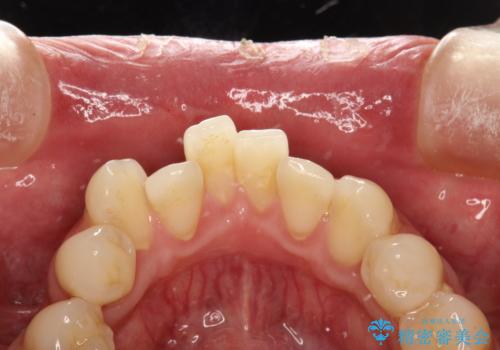

- 治療計画

- 歯科でのクリーニングがかなり久しぶりで口臭も気になるとのことで来院されました。PMTCの60分コースで、染め出し・ブラッシング指導・クリーニングを行いました。

適切な歯磨き方法を習得するには、染め出しを行い、磨き残しを把握していくことがポイントです。

磨けているよう、磨いているつもりでも、汚れが残ってしまうと、毎日の歯磨き時間が無駄になってしまうこともあります。効率的に歯磨きを行い、磨き残しを減らせるように、歯科衛生士による専門的な指導を行います。